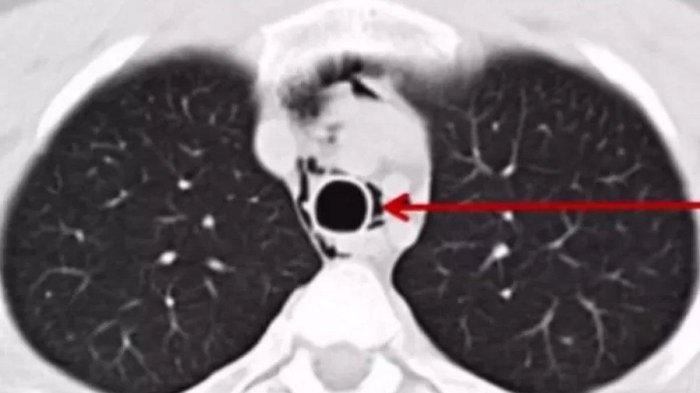

Dilansir Oddity Central pada 24 Juli 2023, remaja berusia 19 tahun itu berteriak dengan antusias selama penampilan band ketika dia tiba-tiba merasakan sakit yang tajam di dadanya.

Dia mulai mengalami kesulitan bernapas segera dan akhirnya pingsan.

Pemuda yang tidak disebutkan namanya itu dibawa ke ruang gawat darurat rumah sakit Shenzen.

Dokter menyimpulkan bahwa dia menderita pecah alveolar di salah satu paru-parunya karena berteriak dengan kekuatan berlebihan selama konser.

Pneumotoraks adalah kumpulan udara abnormal di ruang pleura antara paru-paru dan dinding dada.

Ini dapat terjadi karena cedera dada tumpul atau tembus, kerusakan akibat penyakit paru-paru yang mendasarinya, atau ruptur alveolar karena tekanan yang tiba-tiba atau berat.

Yang terakhir diduga menjadi penyebab kasus pemuda Tionghoa itu, karena ia mengaku berteriak sepuasnya selama konser.

Dokter berhasil menghilangkan kelebihan udara dan mengurangi tekanan pada paru-parunya yang kolaps.